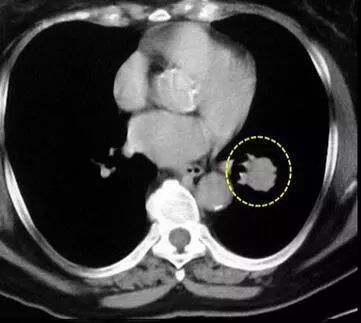

感冒咳嗽长时间不好,或者需要体检,总少不了要做一个肺部的胸片检查,结果有些人拍的片上会发现有一个甚至多个阴影,医生说那是肺部结节。

其实,肺部结节不是疾病的名称,而是拍片所观察到的某些病变的影像学表现的描述。简而言之就是,医生单单只看你肺片里的阴影,是确定不了是什么病的,就用“结节”这个词来描述那些阴影。

①孤立性肺结节:结节表现清晰,边界清楚,且直径小于3cm,周围被肺组织包绕,无症状。

②若结节为纯毛玻璃样,直接不超过0.8cm,多为不典型腺瘤样增生。由于存在发展的可能,应定期复查。

③若结节直径大于3cm,则为肺肿块,则要考虑肺部肿瘤的可能。